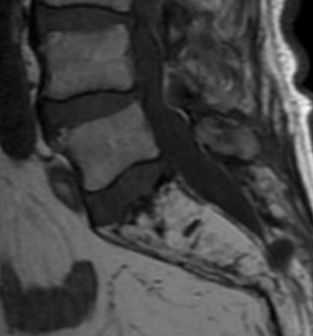

(Слева) МРТ Т1ВИ, сагиттальный срез: определяется диффузное однородное замещение костного мозга. Позвонки характеризуются более низкой интенсивностью сигнала по отношению к межпозвонковым дискам за исключением сохранной жировой ткани вокруг позвоночных вен.

(Справа) МРТ, постконтрастное Т1 ВИ, сагиттальный срез: определяется контрастирование вен и прилегающей жировой клетчатки при отсутствии контрастирования остальной части тел позвонков. Однородность изменений костного мозга и отсутствие контрастирования после введения гадолиниевого контрастного вещества позволяет отличить этот случай от диффузного замещения костного мозга опухолью. (Слева) Рентгенография органов грудной клетки в ПЗ проекции: у пациента с миелофиброзом определяется двустороннее поражение плевры, оказавшееся последствием экстрамедуллярного кроветворения.